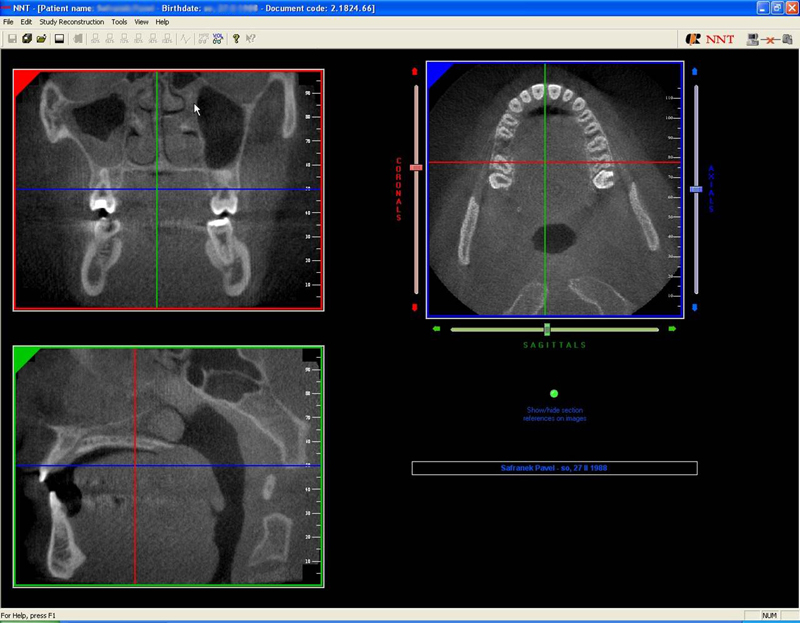

coDiagnostiX – Dental Wings

Jedná se o externí plánovací program, spojený se zubní laboratoří a frézovacím centrem, který využívá dat získaných z 3D rentgenu čelisti, otisku zubů a dásně (scanu zubů a dásně) a finálního návrhu protetické náhrady.

Tento program umožňuje tříprostorovou počítačovou simulaci při plánování pozic implantátů. Součástí programu je i databáze, ve které mohou být uloženy všechny typy implantátů od všech výrobců, včetně jejich délek, průměrů i tvarů.

Lékař si vytvoří všechny typy zobrazení potřebných pro naplánování – tedy 2D snímky (panoramatický), příčné řezy i 3D model.

Vidí zde i důležité anatomické útvary – čelistní dutinu, průběh nervu atd. Po proměření množství kosti – šířky i výšky vybere z databáze vhodný typ implantátu a umístí ho do požadované lokality. Ihned vidí jeho pozici ve všech 3 rovinách a na

všech snímcích i 3D modelu. Může upravovat podle potřeby jeho pozici, sklon atd.

Všechny vybrané a správně umístěné simulované implantáty se ukládají do „počítačové karty“ pacienta s jejich pozicí, délkou, průměrem, typem i sklonem. V programu také lékař navrhuje chirurgické šablony pro řízenou nebo navigovanou implantaci.

Lékař i pacient tedy ještě před vlastní operací vidí, jak by mělo ošetření probíhat a vypadat.